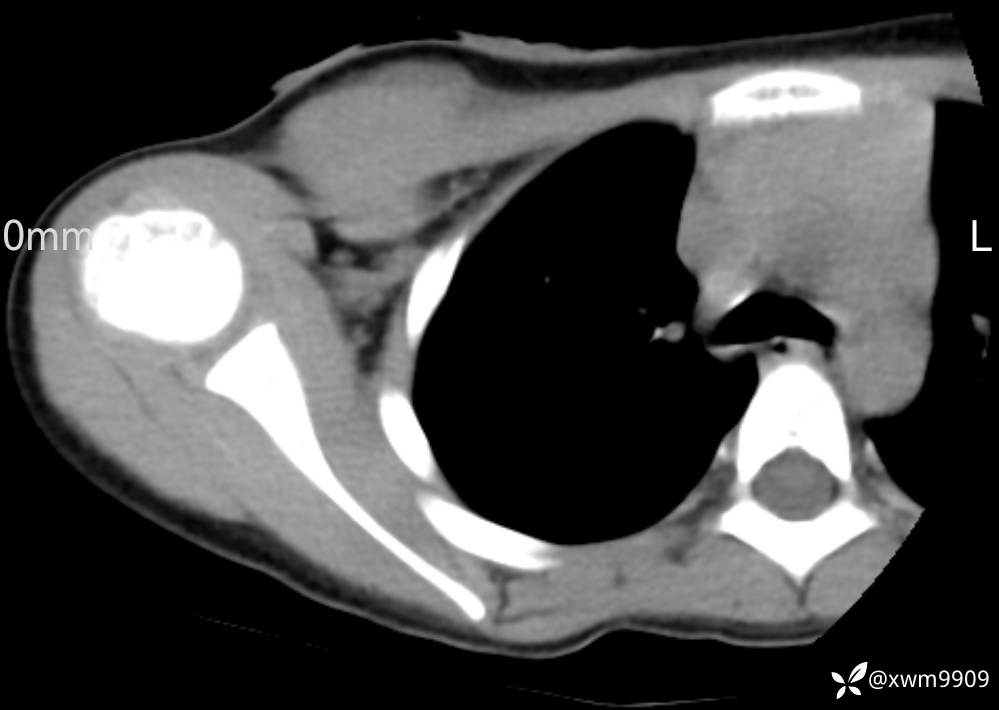

CT:

3、查体,右锁下方可及一约5x6Cm肿物,软丶边清丶未见明显发红,肤温不高,压痛明显,不可推动,稍有波动感。其他无特殊。

2024-03-20,女,6岁。因“发现右侧胸部肿物伴疼痛1天”入院。